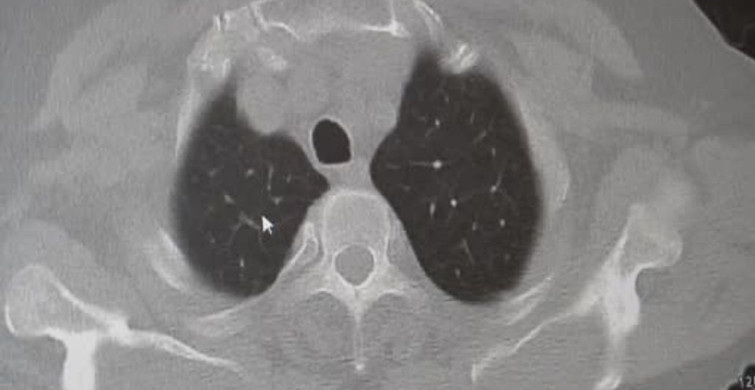

Prof. Dr. Karakurt, KOAH’ın, dünya genelinde ölüm nedenleri arasında 4. sırada yer aldığını belirterek, vakaların %85’inin sigara kullanımı ile ilişkili olduğunu vurguladı. KOAH, zararlı maddelerin akciğerleri etkilemesiyle geliştiği için sigaranın bırakılmasının bu hastalığı önleyebileceğini ifade etti.

MARMARA ÜNİVERSİTESİ PENDİK EĞİTİM VE ARAŞTIRMA HASTANESİ GÖĞÜS HASTALIKLARI KLİNİĞİ’NDEN PROF. DR. SAİT KARAKURT, TOPLUMDA SIK GÖRÜLEN KRONİK OBSTRÜKTİF AKCİĞER HASTALIĞI (KOAH) VE ZATÜRRE HAKKINDA ÖNEMLİ UYARILARDA BULUNDU. KOAH'IN ÖLÜMCÜL HASTALIKLAR LİSTESİNDE ÜST SIRADA YER ALAN VE TOPLUMDA SIK GÖRÜLEN BİR RAHATSIZLIK OLDUĞUNU DİLE GETİREN KARAKURT, "VAKALARIN YAKLAŞIK YÜZDE 85’İ SİGARA KULLANIMINA BAĞLI" DEDİ.